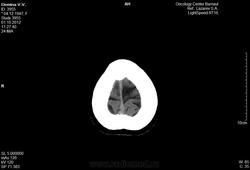

Женщина 64-х лет.

Замыкательные пластинки истончены. Определяется снижение пневмотизации правой гайморовой пазухи за счет утолщения слизистой, слева на нижней стенке гиподесное образование с ровными контурами размером 22мм. Вещество мозга однородной структуры в симметричных участках плотность одинаковая. Среденные образования не смещены. Определяется неравномерное расширение субарахноидальных пространств и усиление борозд больше в лобных и теменных областях.

///верно ли оно?/// Признаков гидроцефалии нет никаких, непонятно на основании чего поставлен гайморит справа, киста в левой верхнечелюстной пазухе есть. По этим снимкам (в этом режиме/окне) оценить состяние костей не представляется возсожным. Скопируйтк с диска dicom-изображения, сархивируйте их, разместите на любом файлообменнике, разместите здесь ссылку. Тогда можно будет посмотреть детальнее.

Наружная гидроцефалия явно надумана за счет верхних нормальных для возраста срезов, а метастаз в кости не определяется в данном окне.

По этим снимкам невозможно оценить, что там в костях. Нужен DICOM. В мозге - умеренная атрофия, соответствующая возрасту.